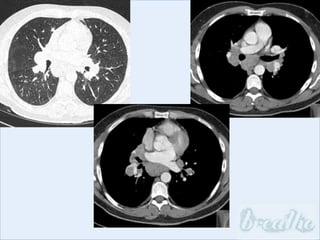

Imaging

Imaging: bihilar and mediastinal lymphadenopathy,

micronodular infiltrates (peri-lymphatic), airspace-like

opacities, ground-glass opacities, peripheral

cavitation, fibrosis